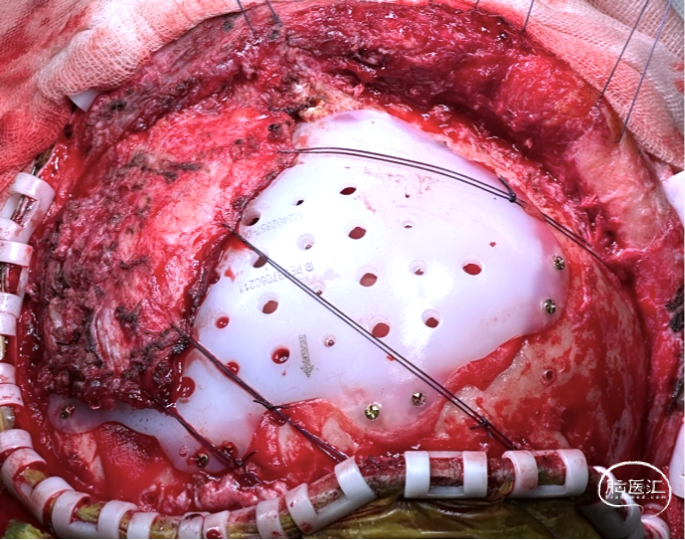

2. 新修补材料植入颞肌下,嵌入骨窗内,恢复正常解剖层次,恢复容貌外观。

修补材料设计方案:UHMWPE网板,标准弧度设计,厚度4mm;与颅骨间隙0.8-1mm;预留孔颞部孔径4mm,其余3mm;采用全覆盖式,翼状结构固定。

手术过程